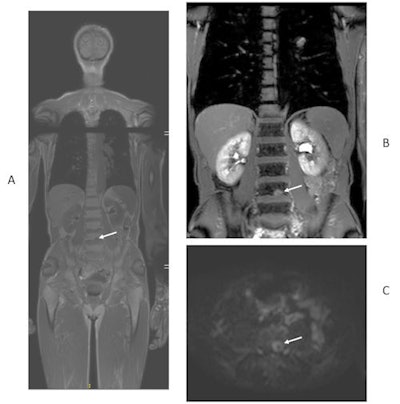

49-year-old man with newly diagnosed lung cancer recruited to Streamline L trial. Whole-body MRI revealed a solitary L4 bone metastasis that was occult on standard imaging, including CT and PET/CT. A = coronal T1-weighted image. B = contrast-enhanced T1-weighted image. C = axial diffusion-weighted image. Figure courtesy of Prof. Stuart Taylor.He thinks the results are equally applicable in the rest of Europe because cancer-staging protocols are largely uniform across the continent. Scan costs are likely to vary between different countries, but Taylor and his colleagues have provided a detailed breakdown of the actual scans performed so other researchers can easily do their own cost analysis.